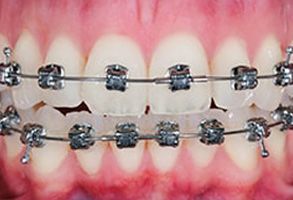

Before

After